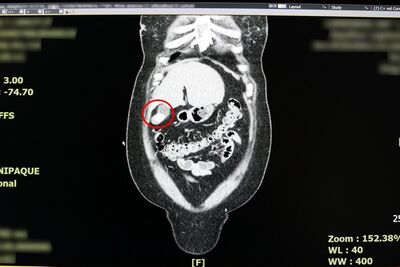

反覆上腹部疼痛時,別再以為只是胃病,當心恐是膽囊炎作祟!一名38歲女性日前因持續2天劇烈上腹痛,先後到診所與地區醫院就診,皆被診斷為胃炎,服藥與打止痛針仍未改善,求診聯新國際醫院急診室,經朱海慶醫師詢問病史與電腦斷層檢查,會診一般外科張堯任醫師,確診為急性膽囊炎。 《詳全文...》